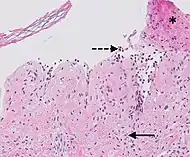

| Kaposi’s sarcoma in patch stage | The patch stage typically shows irregular proliferation of jagged vascular channels in the dermis below an integral epidermis. The so-called promontory sign is sometimes found in patch stage lesions and denotes vascular spaces surrounding pre-existing blood (see image).[23]

vessels |

![]() |